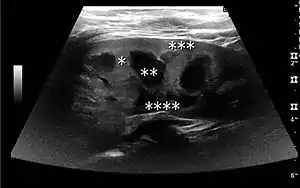

Figure 1. Normal adult kidney. Measurement of kidney length on the US image is illustrated by ‘+’ and a dashed line. *Column of Bertin; ** pyramid; *** cortex; **** sinus.[1]

The kidney is divided into parenchyma and renal sinus. The renal sinus is hyperechoic and is composed of calyces, the renal pelvis, fat and the major intrarenal vessels. In the normal kidney, the urinary collecting system in the renal sinus is not visible, but it creates a heteroechoic appearance with the interposed fat and vessels. The parenchyma is more hypoechoic and homogenous and is divided into the outermost cortex and the innermost and slightly less echogenic medullary pyramids. Between the pyramids are the cortical infoldings, called columns of Bertin (Figure 1). In the pediatric patient, it is easier to differentiate the hypoechoic medullar pyramids from the more echogenic peripheral zone of the cortex in the parenchyma rim, as well as the columns of Bertin (Figure 2).[1]

The length of the adult kidney is normally 10–12 cm, and the right kidney is often slightly longer than the left kidney. The adult kidney size is variable due to the correlation with body height and age; however, normograms for pediatric kidney size are available.[1]

Cortical thickness should be estimated from the base of the pyramid and is generally 7–10 mm. If the pyramids are difficult to differentiate, the parenchymal thickness can be measured instead and should be 15–20 mm (Figure 3). The echogenicity of the cortex decreases with age and is less echogenic than or equal to the liver and spleen at the same depth in individuals older than six months. In neonates and children up to six months of age, the cortex is more echogenic than the liver and spleen when compared at the same depth.[1]